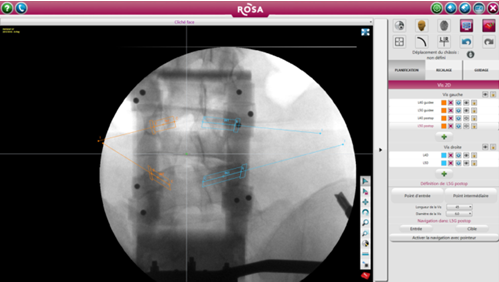

ROSA 是一種影像導(dǎo)航設(shè)備,直接根據(jù)術(shù)中放射線圖像上確定的標(biāo)志或使用導(dǎo)航指針定位工具。引導(dǎo)是基于術(shù)中2D圖像處理軟件完成的軌跡規(guī)劃,隨后患者俯臥位完成注冊(cè)(圖1)。在手術(shù)開始時(shí),沿著患者的右手邊放置機(jī)器人,確保機(jī)器人的手臂能充分地覆蓋兩個(gè)節(jié)段(圖2)。然后外科醫(yī)生站在患者的另一邊。手術(shù)室的組織結(jié)構(gòu)圖如圖3所示。

圖1術(shù)前X線透視下椎弓根螺釘?shù)囊?guī)劃